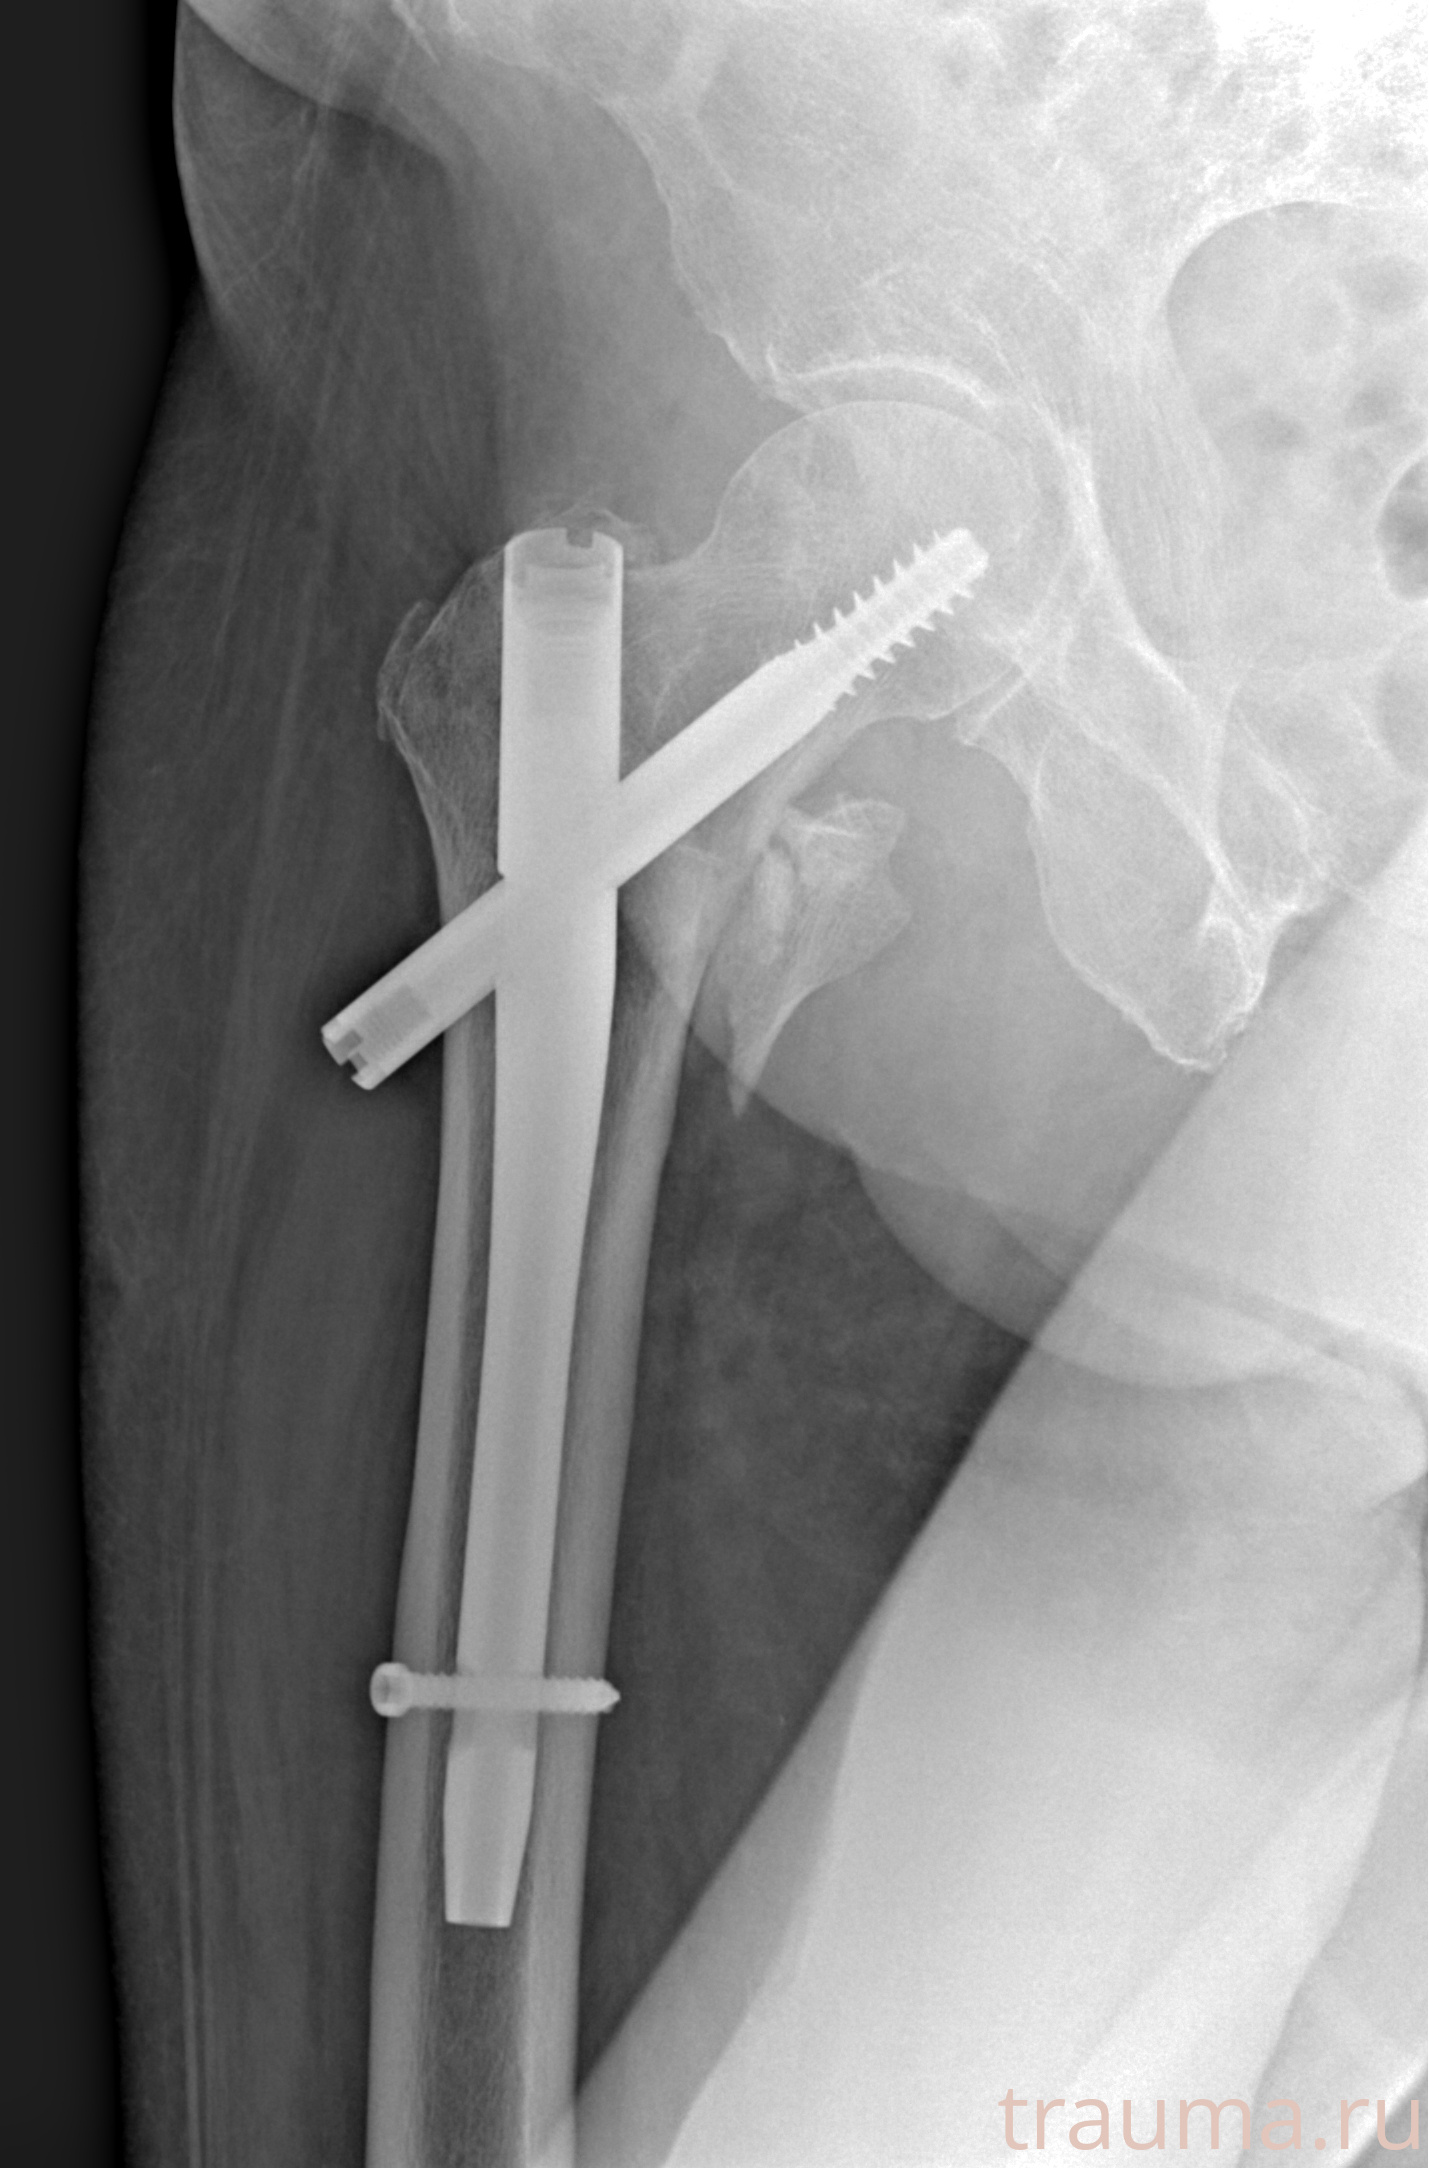

Рентгенограммы

Рентген на дому: по вашему адресу приезжает врач-рентгенолог, травматолог-ортопед с мобильным рентгеновским аппаратом, проводит диагностику травмы или заболевания, делает необходимые рентгенограммы, дает рекомендации по дальнейшему лечению. Получить качественные снимки в домашних условиях возможно благодаря уникальной методике, разработанной МосРентген Центром для института  Склифосовского